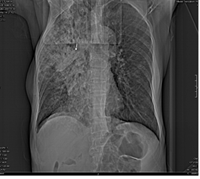

标题: CT9563:女67岁,咳嗽咯白痰伴纳差一月。右肺呼吸音低可闻及 [打印本页]

女67岁,咳嗽咯白痰伴纳差一月。右肺呼吸音低可闻及湿罗音。白细胞及淋巴细胞不高,无发烧

1、右上胸廓塌陷,纵隔气管右移

2、病灶靠后方,一般结核多见一点

3、病灶内,纵隔内有少许钙化灶

3楼的肺细支气管肺泡癌也不能完全排除,毕竟患者年纪大,病史短,临床上感染症状不明显,建议短期内复查吧

病灶范围较大,病史较短,病人年龄较大,结核中毒症状不明显, 考虑1右肺细支气管肺泡癌,2.硬化性淋巴瘤,建议进一步检查